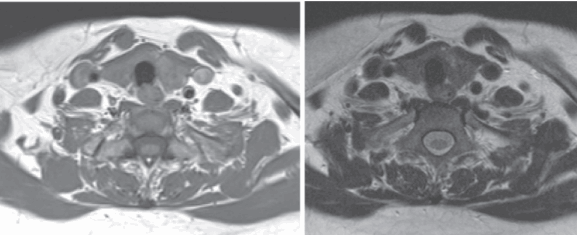

Рисунок 1,2. МРТ мягких тканей шеи (Т2-ВИ и Т1-fs-ВИ контрастное усиление). Патологических образований в структуры щитовидной железы не выявлено.

Снимки МРТ мягких тканей шеи

Мягкие ткани шеи на МРТ